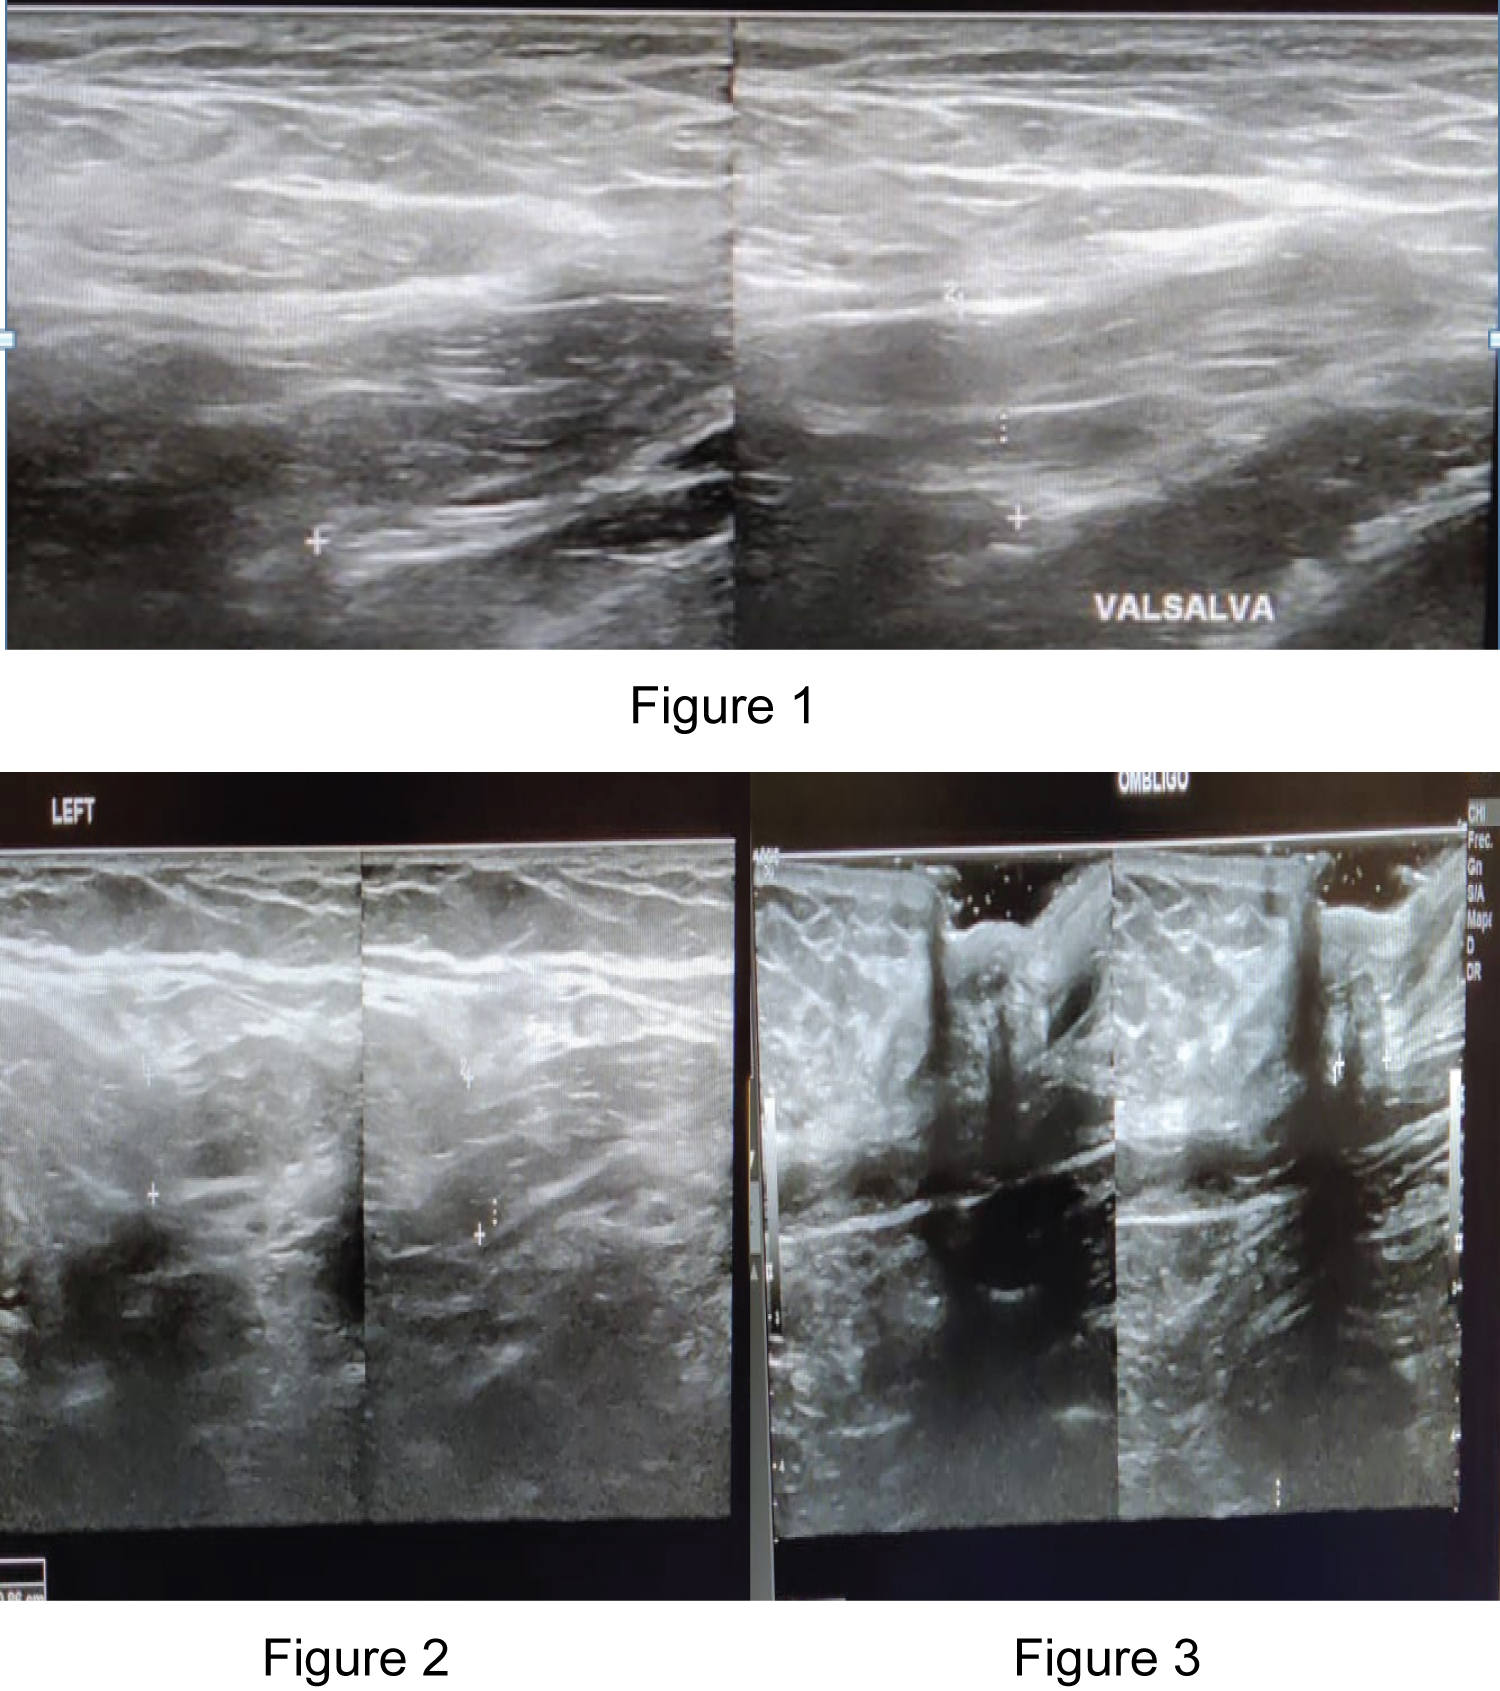

A 63-year-old female with a family history of maternal grandmother with bilateral and umbilical inguinal hernia, father with retinal detachment and inguinal hernia, pathological personal history of essential arterial hypertension, dyslipidemia, and multiple hemangiomas distributed throughout the body. She comes to consult due to increased volume in the right inguinal region for 3 years, in the left inguinal region for two years, both without treatment, which increased with the Valsalva maneuver and currently one in the umbilical region, denying nausea, vomiting, fever, pain or constipation. Physical examination, skin color unchanged, reducible, not incarcerated, not strangled. The diagnostic protocol was started where the presence of bilateral inguinal and umbilical hernia was evidenced, for which a surgical programming was decided to perform abdominal wall plasty (Figure 1, Figure 2 and Figure 3). Right and left inguinal plasty with mesh and umbilical plasty without mesh were performed (Figure 4 and Figure 5). The patient is discharged 24 hours after the procedures were performed. In her follow-up, the patient is asymptomatic and incorporated into her daily activities.

Figure 1, 2 and 3: The diagnostic protocol was started where the presence of bilateral inguinal and umbilical hernia was evidenced, for which a surgical programming was decided to perform abdominal wall plasty. View Figure 1, 2 and 3